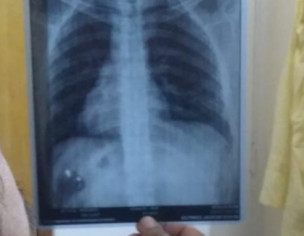

Asking for Brother, Male, 35 years old, Karachi

Pls tell me is there any abnormality in this chest xray and report.

its normal,u may take an app or online appointment

its normal.

if u have any issue u can consult.

plz give detailed history of problem